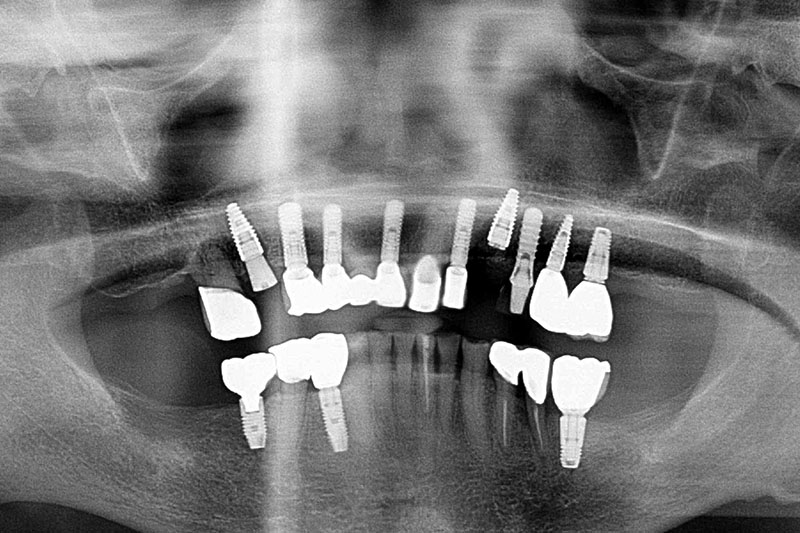

缺牙多顆-全口X光攝影

案例一

術前

術後